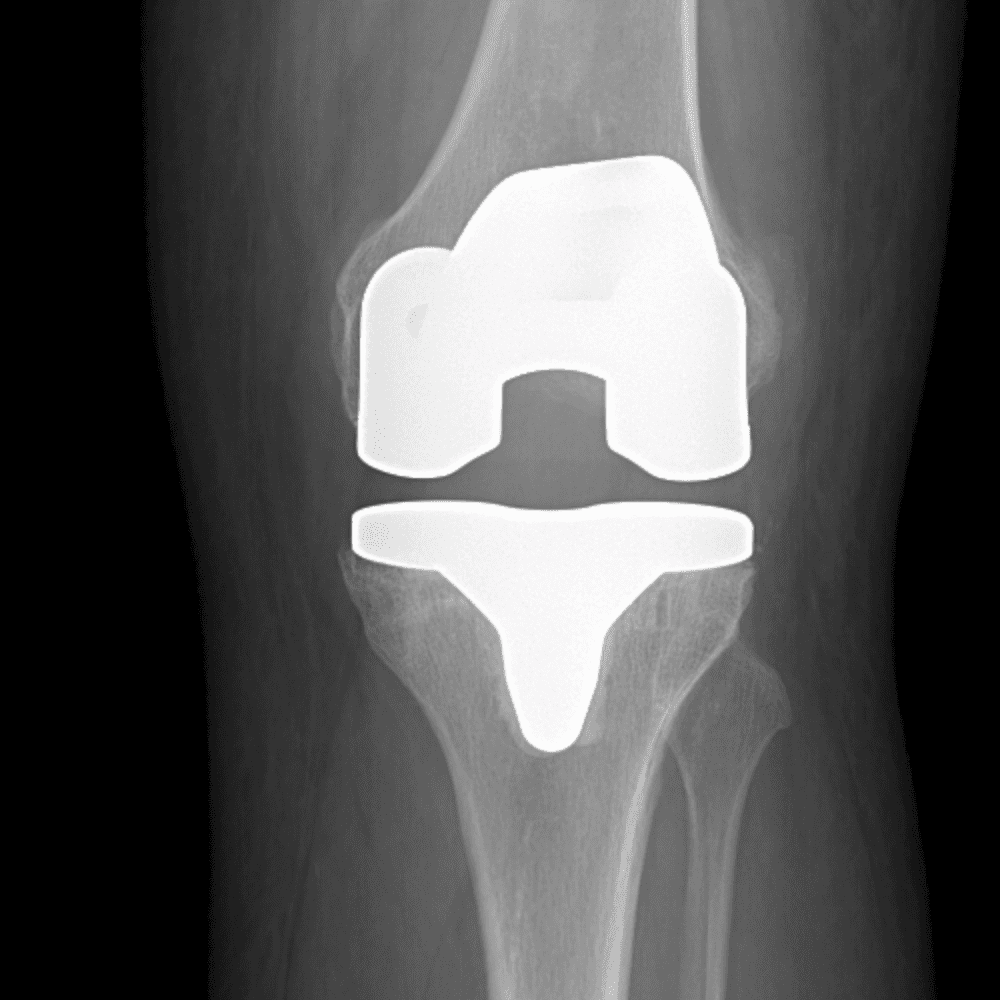

Simula o plantão incluindo casos sutis ou difíceis e alguns normais.